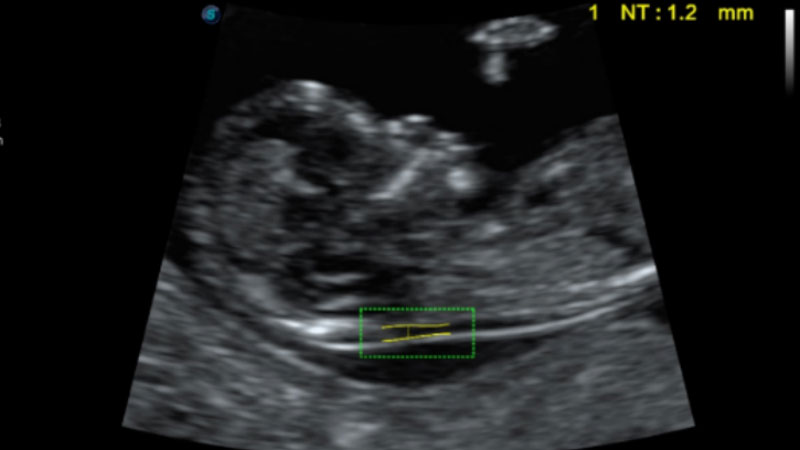

自動識別頸項透明層并獲得NT值,為早孕胎兒畸形篩查提供有效測量工具,提高診斷效率和診斷信心。